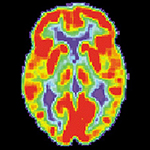

IDEAS Study reaches recruitment goal

In 2016, the Alzheimer's Association launched the Imaging Dementia—Evidence for Amyloid Scanning (IDEAS) Study, the largest ongoing study in dementia research, to test the impact of a brain amyloid positron emission tomography (PET) scan on medical management of people where the cause of their dementia or cognitive impairment is challenging to diagnose. The study has met its recruitment goal to provide more than 18,000 Medicare participants with amyloid PET scans and has closed enrollment ahead of schedule. Learn more.